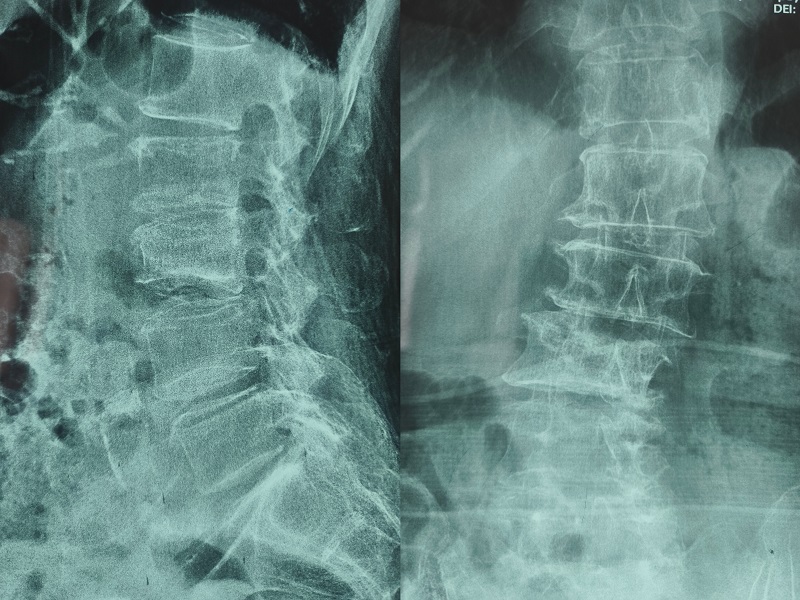

机器人辅助腰椎后路侧弯矫形手术术前图像

术前图像